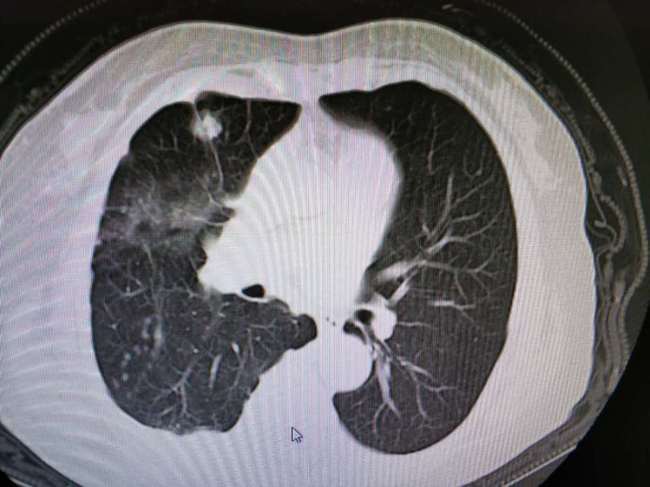

下图是我在肺部影像联盟看到的一个特殊空洞,支气管进入空洞,提示结核

上图所示,这是一个典型的肺结核的空洞(左图),可见不规则空洞与支

肺结核空洞ct图片